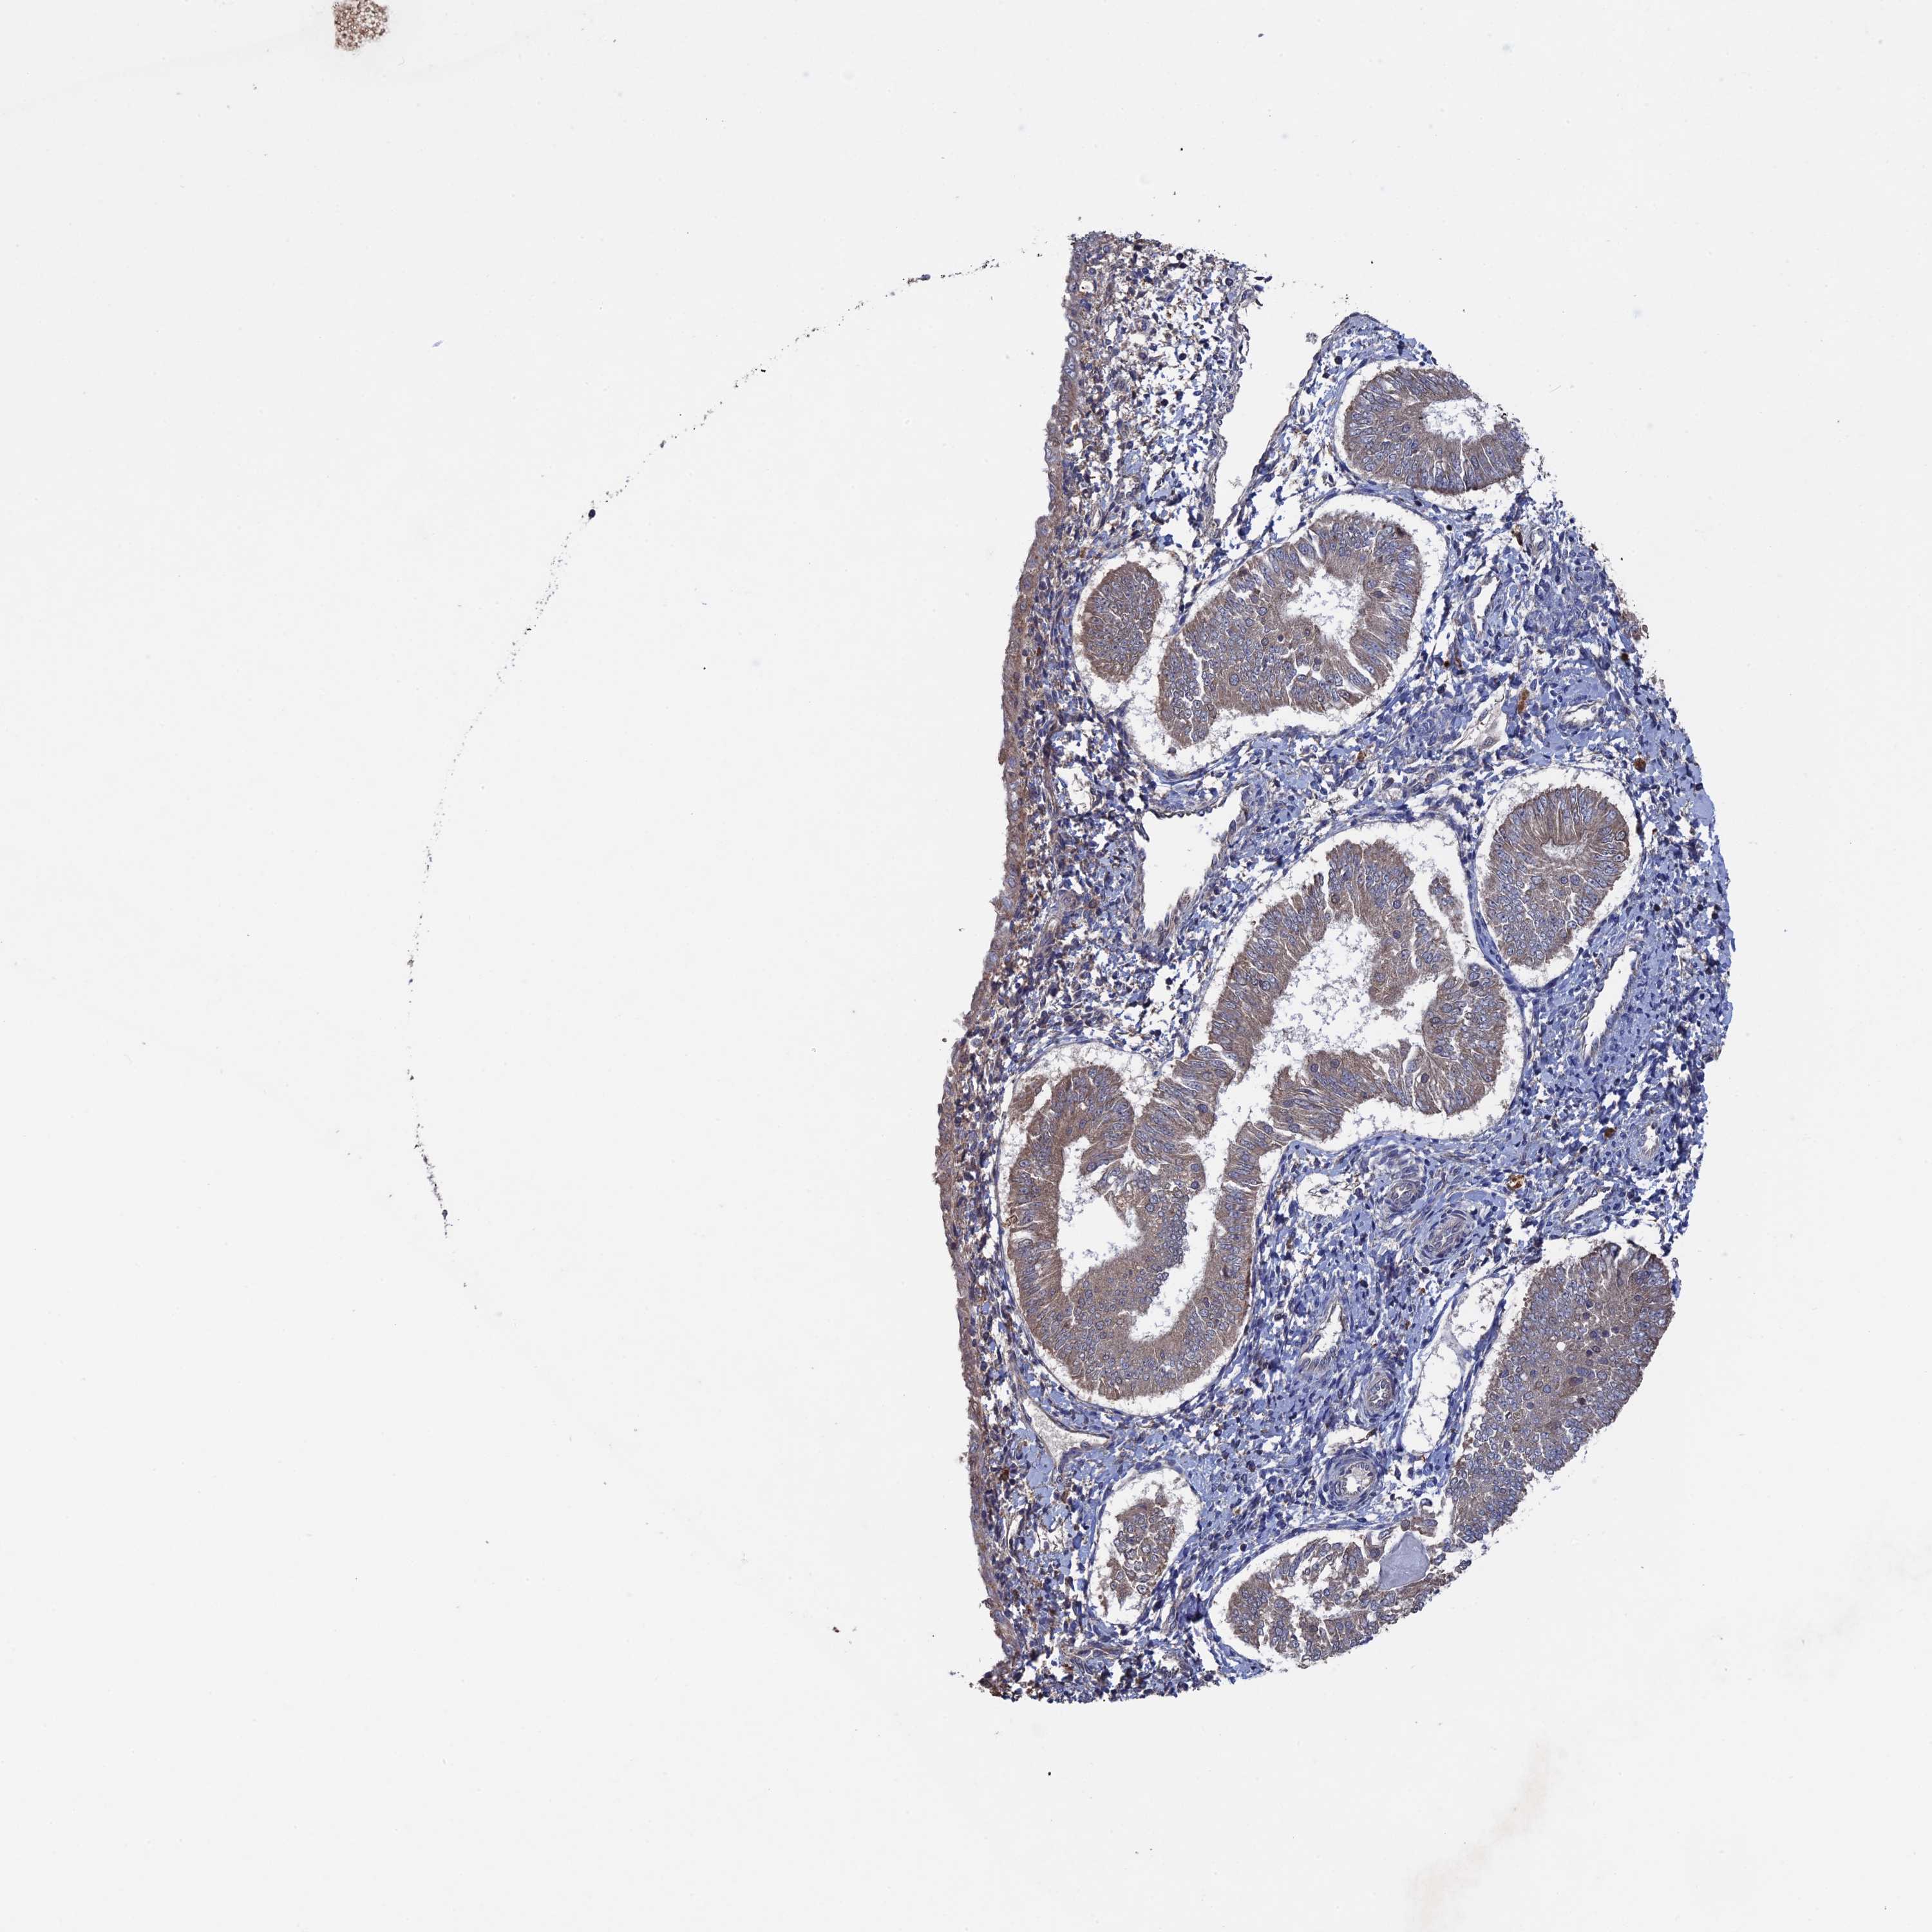

ENDOMETRIAL CANCER - Protein expressioni

A mouse-over function shows sample information and annotation data. Click on an image to view it in a full screen mode. Samples can be filtered based on level of antibody staining by selecting one or several of the following categories: high, medium, low and not detected. The assay and annotation is described here.

Note that samples used for immunohistochemistry by the Human Protein Atlas do not correspond to samples in the TCGA dataset.

Antibody stainingi

Antibody staining in the annotated cell types in the current human tissue is reported as not detected, low, medium, or high, based on conventional immunohistochemistry profiling in selected tissues. This score is based on the combination of the staining intensity and fraction of stained cells.

Each image is clickable and will lead to virtual microscopy that enables deeper exploration of all samples and also displays staining intensity scores, fraction scores and subcellular localization as well as patient and tissue information for each sample.

Antibody HPA041177

Staining

High

Medium

Low

Not detected

Intensity

Strong

Moderate

Weak

Negative

Quantity

>75%

75%-25%

<25%

None

Location

Nuclear

Cytoplasmic/membranous

Cytoplasmic/membranous,nuclear

Adenocarcinoma, NOS